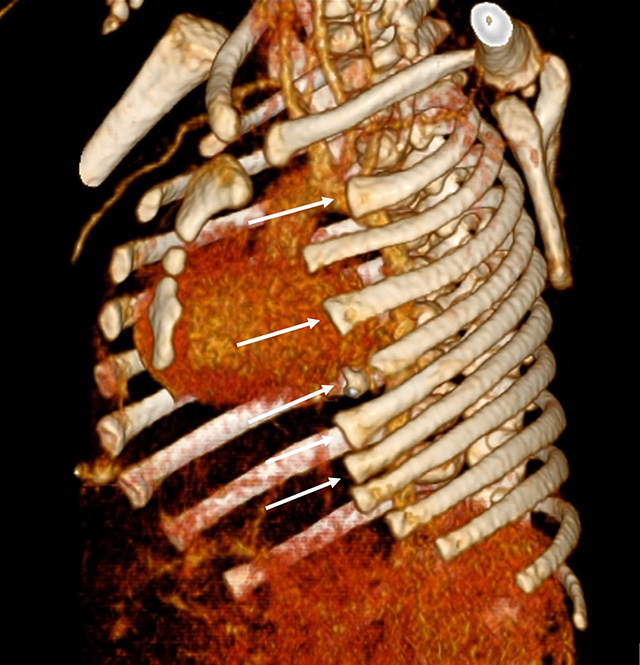

Figure 5

3D reconstruction of the chest CT-scan shows partial agenesis of the anterior arches of ribs 2, 4 to 7 on the left side (white arrows).